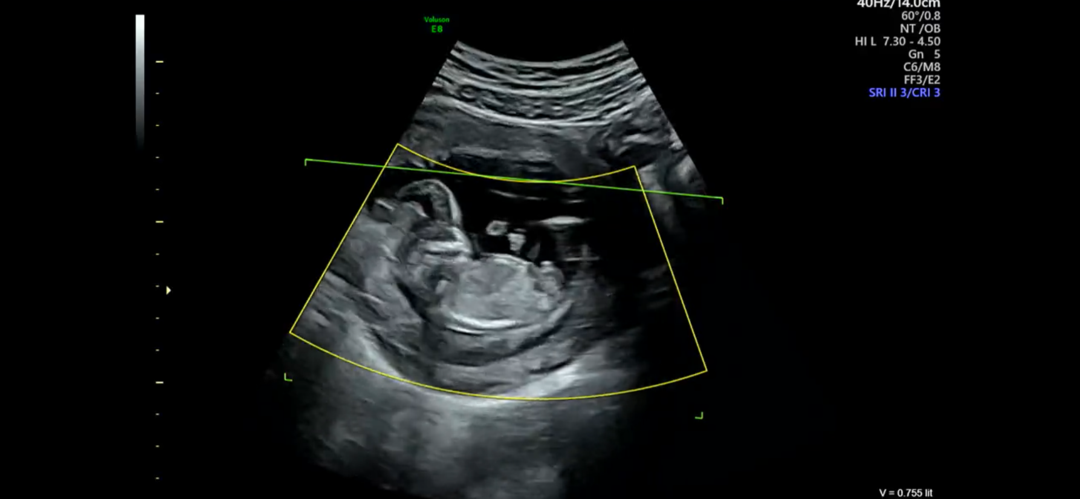

13주 각도법 고수님들 도와주세요...! 😇

각도법 고수님들이 보시기엔 성별이 어떻게 보이시나요...? 🥹🥹

아들이욤 !